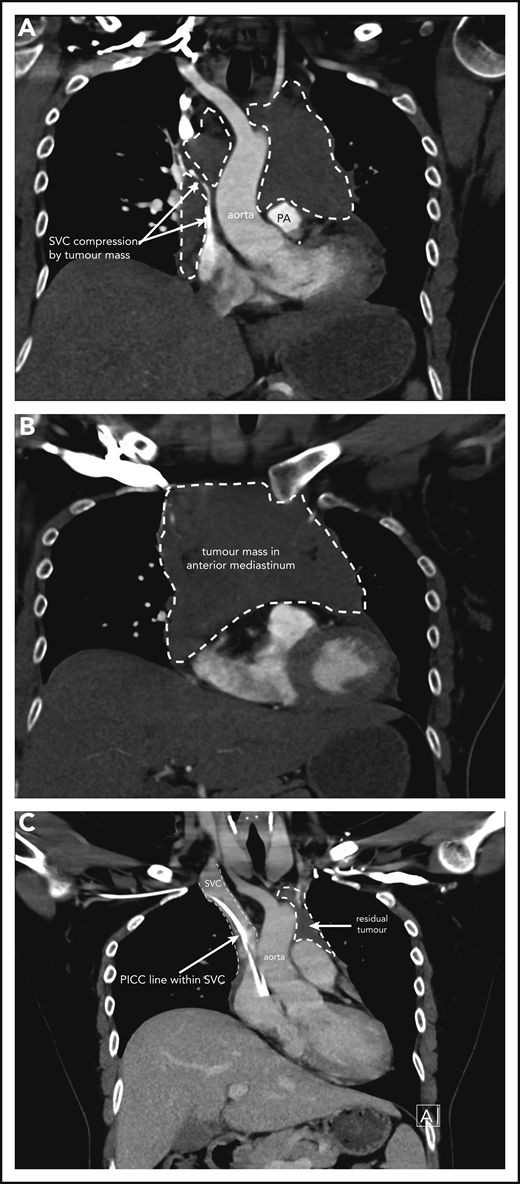

A 37-year-old woman, in her second ongoing pregnancy, presents to the emergency room at 30 weeks and 6 days (30+6 weeks) gestation with a history of chest pain and shortness of breath that woke her from sleep. She also has cramps in her right calf. She has been experiencing increasing shortness of breath and palpitations when mobilizing over a few weeks. She is a nonsmoker who drinks no alcohol. There are no concerns with her baby, and her first pregnancy and birth were uncomplicated. On examination, she is tachycardic at 120 beats per minute, normotensive with a blood pressure of 114/60 mm Hg, oxygen saturations of 97% on room air, and afebrile. Distended jugular veins are noted bilaterally, and she has no chest wall tenderness. Chest auscultation revealed crackles in the right lower zone. Heart sounds are dual with no murmurs. She has no lymphadenopathy, and abdominal examination reveals an enlarged uterus as expected for her dates with no other abnormalities. Complete blood count is normal. A comprehensive metabolic panel is normal other than an elevated lactate dehydrogenase (448 U/L; reference range, 120-250 U/L) and C-reactive protein (70 mg/L; reference range, 1-5 mg/L). The initial clinical concern for a pulmonary embolism prompted a computed tomography (CT)-pulmonary angiogram. This shows a large mediastinal mass measuring 11.5 × 8.3 × 8.3 cm causing significant obstruction of the superior vena cava and left main pulmonary artery and narrowing of the left upper lobe bronchi (Figure 1A-B). A small pericardial effusion is noted. Differential diagnosis includes lymphoma with other possibilities of thymic neoplasm, teratoma, or thyroid malignancy. A CT-guided biopsy of the mediastinal mass is performed and confirms focal areas showing proliferation of medium to large lymphoid cells. The large lymphoid cells are positive for CD20, CD79a, and PAX5, as well as BCL6, and have weak BCL2 staining. CD23 and CD30 show weak patchy positivity in the large cells and CD10, CD15, MUM1, cyclin D1, and Epstein-Barr virus in situ hybridisation (ISH) are negative. The Ki67 proliferative fraction is 60%. Fluorescence in situ hybridization studies reveal no rearrangement of MYC, BCL2, or BCL6. Pathologic features are consistent with a diagnosis of PMBCL.

Case 1 of patient with primary mediastinal B-cell lymphoma presenting at 31weeks gestation. (A) Coronal section chest CT scan with contrast at diagnosis, pretreatment. Illustrates significant compression of SVC by tumor mass (within broken lines) on right and demonstrating extent of mass also on left superior to pulmonary artery (PA). (B) Transverse section chest CT scan with contrast at diagnosis, pretreatment. Illustrates extent of anterior mediastinal tumor mass. CT imaging suggested possible moderate-sized pericardial effusion found on echocardiography to be a small effusion. (C) Coronal section chest CT scan with contrast at completion of treatment. Normal caliber SVC with a peripherally inserted central catheter (PICC) line in situ. Small volume of residual tumor (within broken lines). Subsequent PET-CT scan demonstrated no activity confirming a complete metabolic response.

Case 1 of patient with primary mediastinal B-cell lymphoma presenting at 31weeks gestation. (A) Coronal section chest CT scan with contrast at diagnosis, pretreatment. Illustrates significant compression of SVC by tumor mass (within broken lines) on right and demonstrating extent of mass also on left superior to pulmonary artery (PA). (B) Transverse section chest CT scan with contrast at diagnosis, pretreatment. Illustrates extent of anterior mediastinal tumor mass. CT imaging suggested possible moderate-sized pericardial effusion found on echocardiography to be a small effusion. (C) Coronal section chest CT scan with contrast at completion of treatment. Normal caliber SVC with a peripherally inserted central catheter (PICC) line in situ. Small volume of residual tumor (within broken lines). Subsequent PET-CT scan demonstrated no activity confirming a complete metabolic response.

Case 1 follow-up

The patient initially received high-dose steroids for treatment of her SVC syndrome once the diagnosis was made. She then received her first cycle of DA-EPOCH-R therapy at 33+3 weeks of gestation and tolerated it very well. Additionally, growth colony-stimulating factor was administered with no complications. An MRI of the chest was performed 2 weeks later and showed reduction in the size of the mediastinal mass to 8.6 × 4.5 × 5.4 cm with significant improvement in SVC and airway compression. Labor was induced at 35+5 weeks, and our patient had an uncomplicated vaginal birth to a healthy girl (birth weight, 2585 g) who had no neonatal complications. She received her second cycle of DA-EPOCH-R on day 22 as per the chemotherapy regimen without complication on the fourth postpartum day and subsequently completed a total of 6 cycles of therapy. CT and FDG-PET scans were done at completion of therapy, showing significant shrinkage of the mass on CT (Figure 1C) and complete metabolic response on FDG-PET, and she did not require consolidation mediastinal radiation. She remains in complete remission at last follow-up.